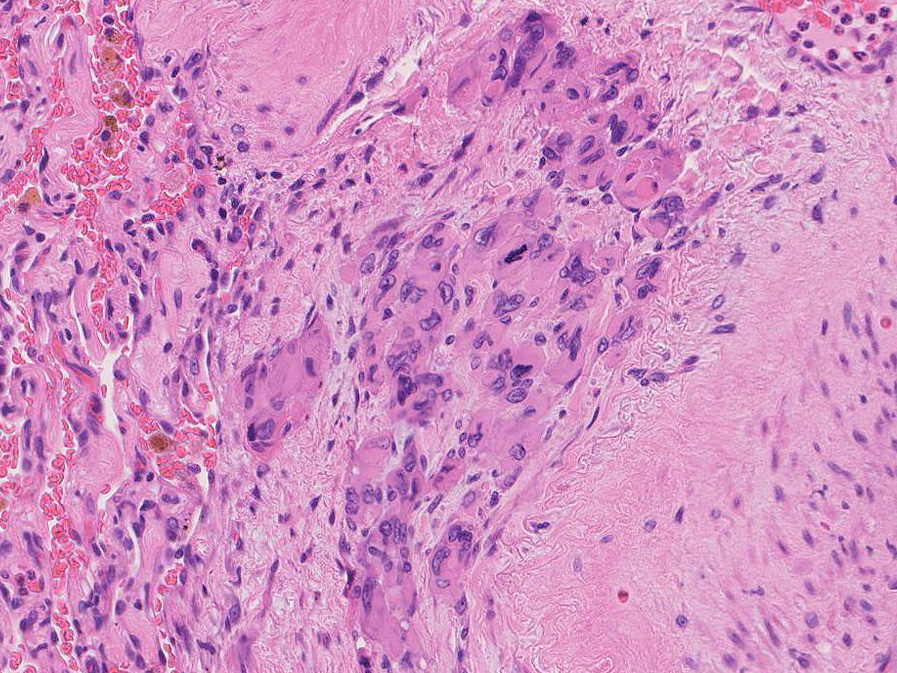

直径5-6mmの, 中央に弾性線維をふくむfibrous noduleがあり, 腫瘍細胞は結節の辺縁部に沿って認められる。

hyperchromaticな類円ないし多角の核で好酸性の広めの細胞質をもつ上皮様細胞が増殖している。右図では血管内を占拠するように腫瘍細胞が認められる。

左図:腺腔様の裂隙が胞巣内にみられ, 凍結標本だと腺癌との区別がむずかしい。

右図:多型細胞や異型細胞が出現。核分裂像も異常に見える。